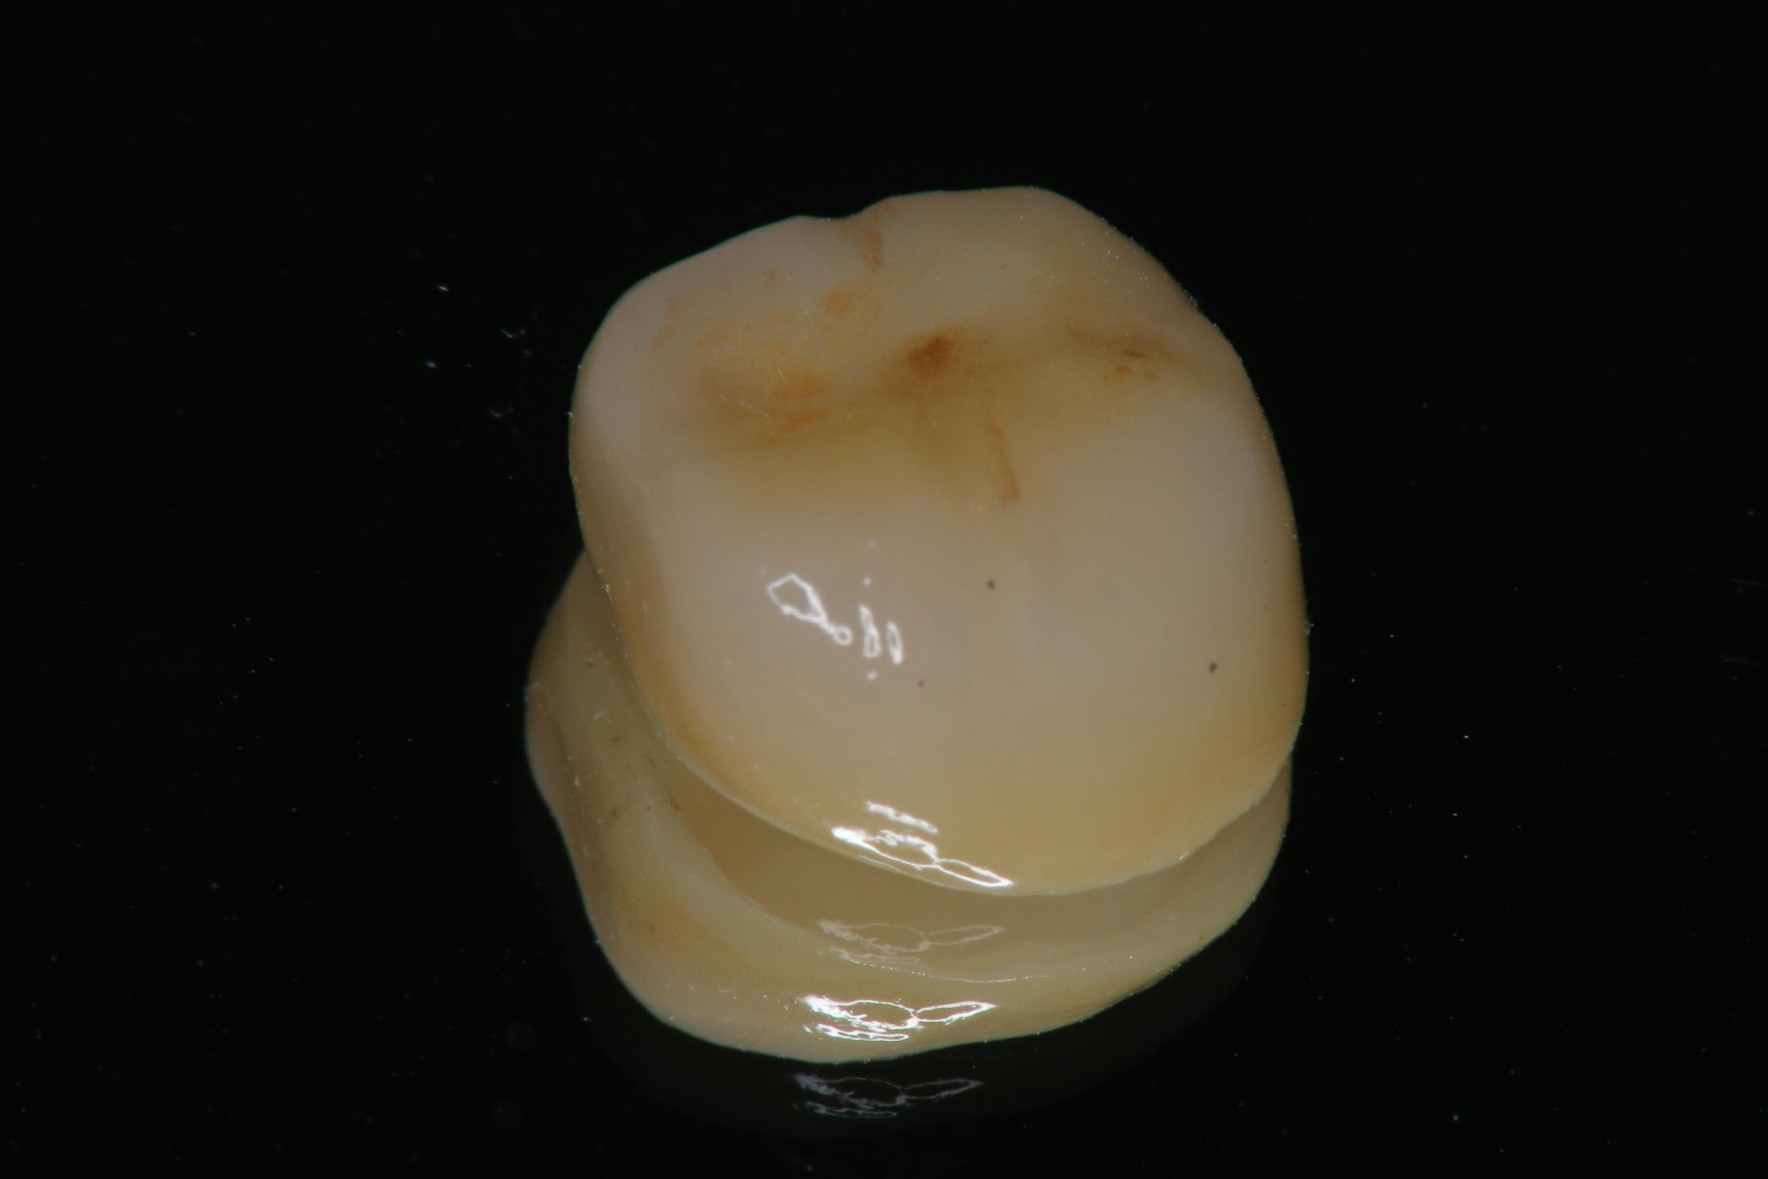

全鋯冠